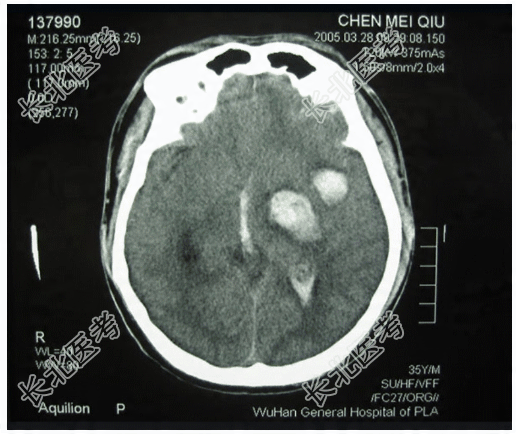

- 多项选择题1.提示:CT片,见下图。可得出的诊断有

A、左侧颞叶脑挫裂伤

B、脑室内出血

C、左侧颞叶脑内血肿

D、左侧颞叶胶质瘤

E、弥漫性脑水肿

F、胶质母细胞瘤